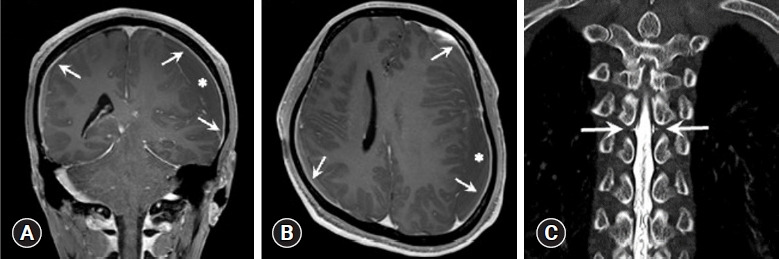

This case series highlights chronic subdural hematoma in previously healthy young and middle-aged patients, where symptoms persisted despite initial surgical intervention. Subsequent diagnosis revealed spontaneous intracranial hypotension through computed tomography myelography. All patients experienced symptom relief after undergoing epidural blood patch. In conclusion, spontaneous intracranial hypotension should be considered in chronic subdural hematoma cases without trauma or underlying disease, with epidural blood patch recommended before surgical intervention if spontaneous intracranial hypotension is suspected.

Abstract Image